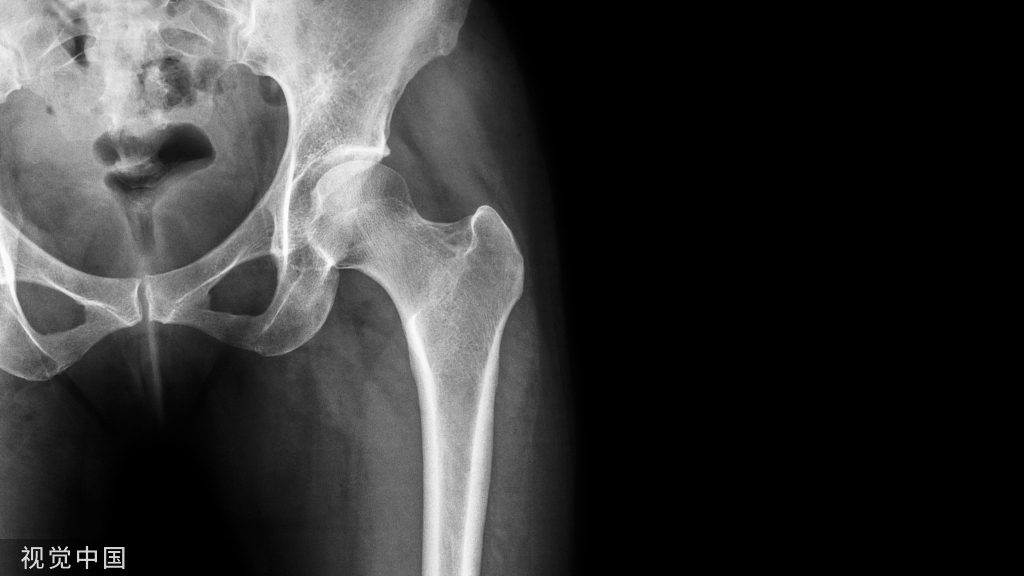

(四)、髋部手术的体位(全髋、半髋置换) 侧卧位

- 患者健侧卧位,头偏向一侧置头圈。

- 腋下垫一腋垫,双上肢用束臂带固定于双层搁手架上。

- 在耻骨联合和骶尾部用体位固定架固定,在体位固定架和身体间加一软垫保护。

- 健侧下肢弯曲,在膝关节处及踝关节处垫一脾垫,大腿上放一海绵垫约束带固定。

(五)、股骨动力髋、动力髁、空心钉、三针、钢板手术的体位

- 患者平卧位,头下置头圈,健侧上肢用束臂带固定于搁手架上,患侧上肢加软垫保护置于胸前或头部。

- 髋部垫一小方垫,约抬高患处15°~30°充分暴露术野。

- 健侧下肢膝下及足下垫一方垫,膝部放一海绵垫约束带固定。